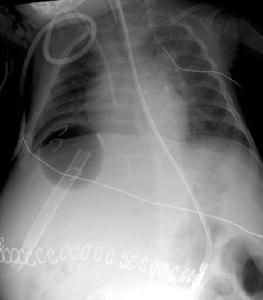

1.腦水腫當有踝陣攣、錐體束征陽性時已有腦水腫,或有球結膜水腫、瞳孔散大固定,呼吸變慢、節律不規則,視乳頭水腫均示腦水腫表現。

2.凝血功能障礙和出血出血部位以皮膚、齒齦、鼻黏膜、球結膜及胃黏膜等常見。

3.感染以呼吸道感染最常見,其他發泌尿感染,多為G-桿菌、G+球菌,也可有厭氧菌及黴菌感染。

4.腎功能衰竭FHF時腎功能異常達70%,急性腎小管壞死占半數。有高尿鈉、等滲尿及腎小管壞死。與肝細胞壞死、內毒素血症、利尿劑套用不當、胃腸出血致低血容量及低血壓等因素有關。有報告腎功能衰竭在FHF死因中占首位,值得注意。

6.其他低血糖、低氧血症、肺水腫、心律失常、門脈高壓及急性胰腺炎等。